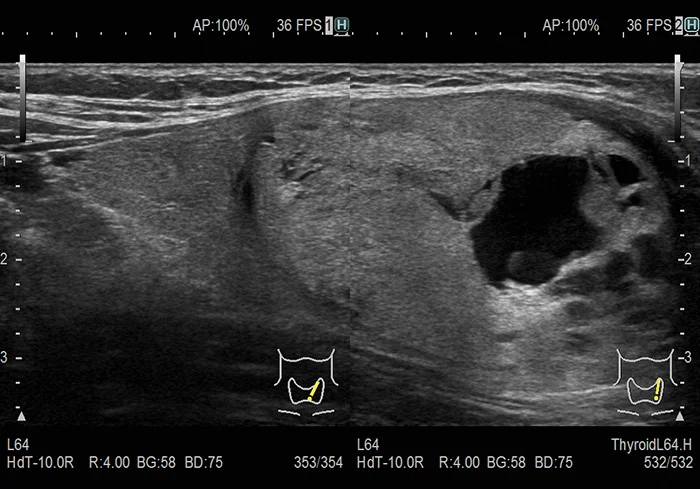

Резная визуализация в ультразвуке

Технология Carving Imaging (или «Резная Визуализация») – это методика обработки изображений, позволяющая лучше различать структуры живых тканей. Чёткая визуализация с пониженным уровнем шума вносит значительный вклад в упрощение диагностики.